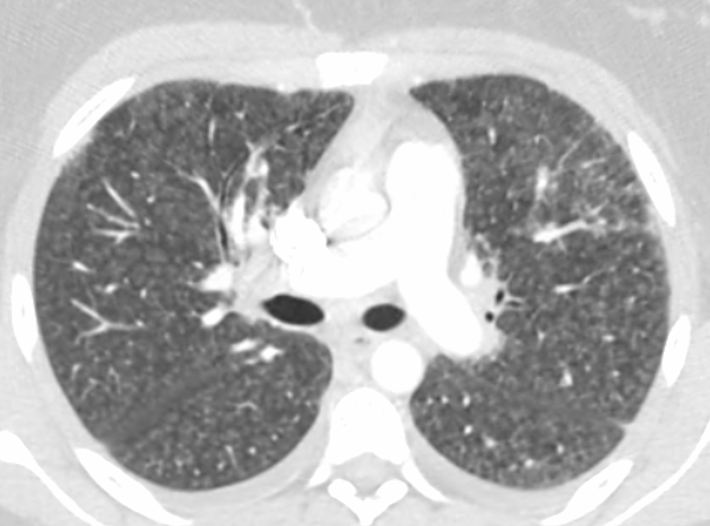

Two days after her initial presentation, the patient returned to the same outside ED for worsening dyspnea. At that second visit, she was again found to be hypoxic, with oxygen saturation levels ranging from 85% to 87% requiring supplemental oxygen at 3 L/min via a nasal cannula. She was admitted again. CT scans of the chest now showed a significant increase in interstitial infiltrates and some hilar and mediastinal lymphadenopathy, along with small diffuse bilateral interstitial opacities representing pleural effusions (Figure).

Figure. CT scans at the patient’s second ED visit showed a significant Increase in interstitial infiltrates with mediastinal and hilar adenopathy and small bilateral pleural effusions, findings concerning for infection.